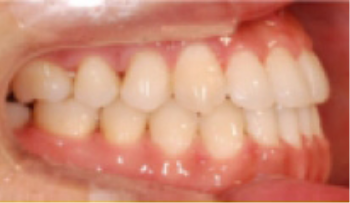

• 총생(Crowding) 치아가 삐뚤게 남.

Before

After